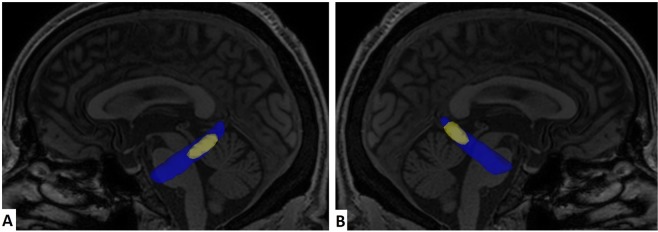

Cingulum in the hippocampal formation

Considering only voxels on the hippocampal cingulum whose training samples indicate a decrease in FA values from healthy controls to AD patients, SVM achieved average accuracies of 87% between AD and controls, 83% between AD and MCI, and 57% between MCI and controls. Considering only voxels whose training samples indicate an increase on FA from healthy controls to AD patients, SVM achieved accuracies of 47% for all three binary permutations of subject groups. Therefore, the discriminative voxels in the bilateral hippocampal cingulum show a decrease in FA values in AD patients. Applying feature selection on the voxels inside the bilateral hippocampal cingulum, the set of voxels whose Fisher Score was higher than 0.4 (Fig. 2) reached the highest accuracy at 93% between AD and controls. The set of voxels whose Fisher Score was higher than 0.8 attained an accuracy of 87% between AD and MCI, and 63% between MCI and controls (Fig. 3).

Figure 2.

Voxels inside bilateral hippocampal cingulum (blue), and those whose Fisher Score was higher than 0.4 (yellow). (A) Left view. (B) Right view.